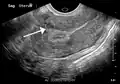

A very large (9 cm) fibroid of the uterus which is causing pelvic congestion syndrome as seen on ultrasound

A small uterine fibroid seen within the wall of the myometrium on a cross-sectional ultrasound view